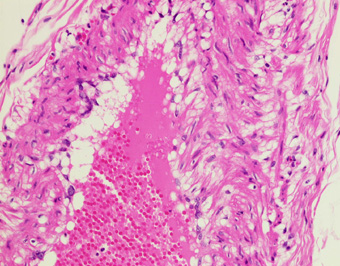

漿膜下層の静脈壁の平滑筋細胞に空胞変性をみとめる.(HE,×20) |